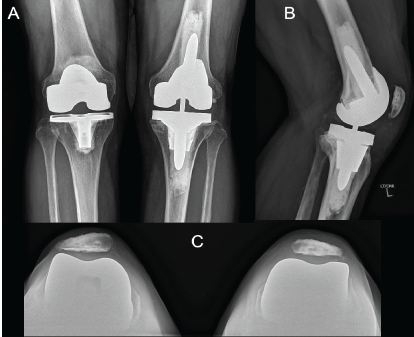

A Novel Seven-Day Abbreviated Two-Stage Exchange Arthroplasty with Intra-Articular Antibiotic Irrigation for Chronic Periprosthetic Joint Infection of the Knee: A Case Report

Nicolas S Piuzzi , Ignacio Pasqualini , Shujaa T Khan , Bryan D Springer , Brian C De Beaubien

………………………………p.119-125